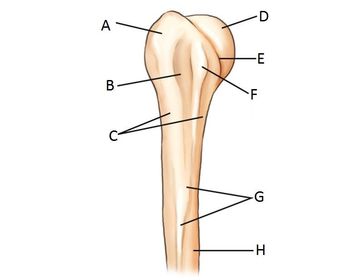

Question Answer

A. greater tubercle (tuberosity) B. intertubercular groove (bicipital) C. surgical neck D. head E. anatomic neck F. lesser tubercle (tuberosity) G. deltoid tuberosity H. humeral body (shaft)